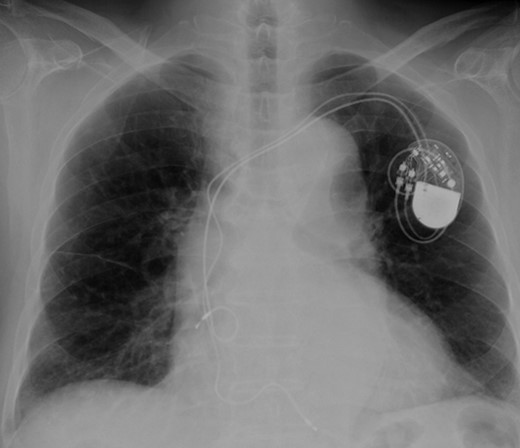

Eight years ago, a DDD pacemaker was implanted in an elderly man due to complete atrioventricular (AV) block. The pacing sites were the appendage of the right atrium and the apex of the right ventricle (Fig. 1) subsequently he suffered PICM with an LV ejection fraction of 37% and obvious dyssynchrony. He had chronic heart failure of NYHA II. Suddenly, the patient developed fever and complained of difficulty eating. Transthoracic echocardiography showed a vegetation (11 × 12 mm2) at the pacemaker leads, and this vegetation was also attached at the tricuspid valve (Fig. 2). Laboratory examination showed elevated white blood cell count and C reactive protein levels. He was diagnosed with PAIE, although the peripheral blood cultures showed no bacteria. After antibiotic therapy, laboratory examination showed decreasing inflammation parameters, but the size of the vegetation remained stable.